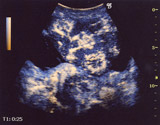

早期相のHybrid Angio画像

(末梢型胆管癌肝内多発症)

提供:

医療法人ロコメディカル江口病院

小野尚文院長

今回受賞した技術は,「Hybrid Contrast Imaging(ハイブリッド・コントラスト・イメージング)」。日本初の超音波診断用低音圧造影剤「ソナゾイド® 注射用(以下,ソナゾイド)※1」に対応したフルデジタル超音波診断装置「LOGIQ 7(ロジック・セブン)」に搭載した技術。ソナゾイドから得られた超音波信号を,血流由来のものと,組織還流由来のものとに分別し,それらの信号を着色してBモード※2に重ねて表示できるようにした。これにより,造影像と通常の断層像とを同時に観察可能となり,診断時の利便性向上に大きく貢献する。